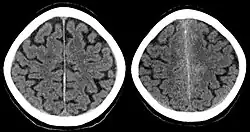

Der Hydrocephalus entsteht manchmal sofort nach subarachnoidaler Einblutung, manchmal aber auch Tage später. Er ist im Computertomogramm (CT) sehr gut darstellbar. Da ein Hydrocephalus sehr gefährlich ist, muss bei dieser Verdachtsdiagnose sofort ein CT angefertigt werden. Ein Hydrocephalus entwickelt sich innerhalb der ersten 3 Wochen nach dem Initialereignis.

Computertomografie

Die Computertomografie (CT) des Kopfes (cCT) ist die derzeit schnellste Methode zur Diagnose einer Subarachnoidalblutung. Sie hat die höchste Sensitivität (100 Prozent am ersten Tag der Blutung[12]) und Spezifität aller bildgebenden Verfahren und ist unter modernen Bedingungen – unter Verwendung eines Spiral-CT mit geringen Belastungen – für den Patienten schnell und sicher durchführbar. In 70 Prozent der Fälle lässt sich schon in einer ersten Aufnahme die Blutungsquelle vermuten. CT-Untersuchungen sollten sofort erfolgen. Bei derartigem Vorgehen wird rasches therapeutisches Handeln ermöglicht, da eine Nachblutung lebensgefährlich wäre und deshalb vermieden werden muss. Die Einteilung nach Fisher[13] erlaubt eine Klassifikation der computertomografischen Morphologie:

- Grad 1: kein Hinweis auf Blutung

- Grad 2: Subarachnoidalblutung von weniger als 1 mm Breite

- Grad 3: Subarachnoidalblutung von mehr als 1 mm Breite, jedoch ohne Ventrikeleinbruch

- Grad 4: Subarachnoidalblutung jeder Breite mit Ventrikeleinbruch (IVH) oder Ausdehnung ins Gehirnparenchym